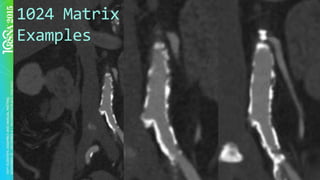

§  Recon	larger	matrix	–	1024x1024

1024	Matrix

Examples